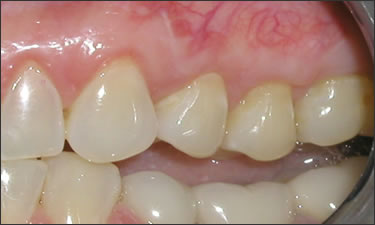

This young patient was self-conscious about the appearance of her short teeth and gummy smile. Through crown lengthening and tooth whitening procedures, we were able to create a beautiful, more mature smile.